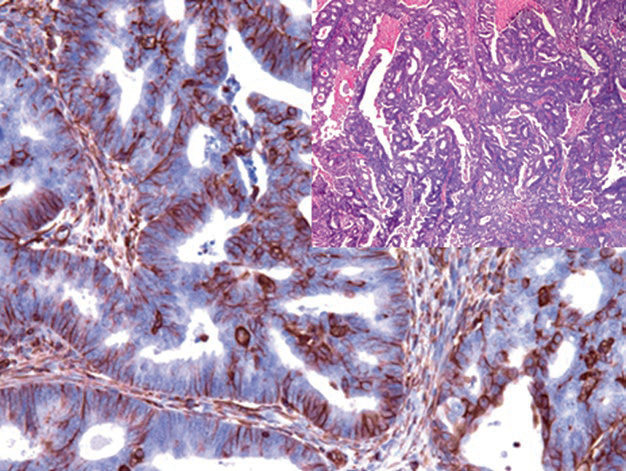

Figure 1. In endometrial carcinoma, the tumor glands strongly express Vimentin.